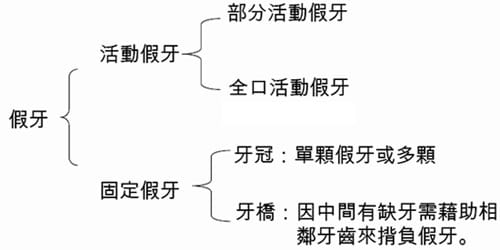

Sunny一直以為… 作假牙是這樣的(如下,不過這圖少了植牙?)

Sunny原以為做一顆單顆假牙就要犧牲旁邊兩顆健康的牙齒

殊不知… 如果牙根情況良好其實可以只做單一顆牙冠假牙即可

所以李醫師解說下,Sunny才了解自己要做的是這樣(如下)